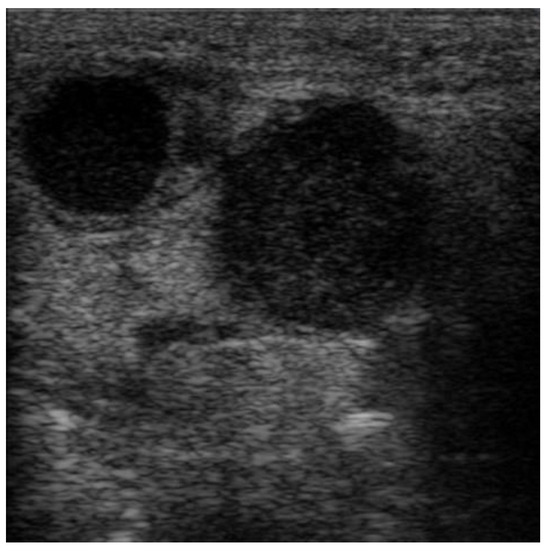

The images were exported from the device used in .jpg format (Figure 1) directly from the US machine and processed by cropping them and resizing them to 469 × 469 pixels (Figure 2).

Figure 2. Processed image, cropped and resized to 469 × 469 pixels.